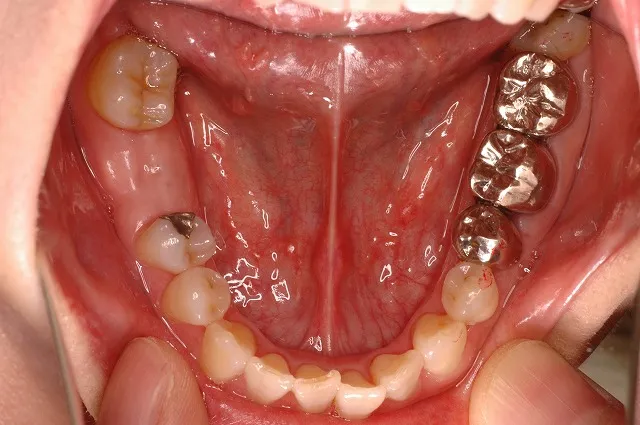

症例5

右下7:抜歯後、インプラント埋入+セラミックメタルボンドクラウン

右下6:セラミックメタルボンドクラウン

左下6:ハイブリッドセラミックインレー